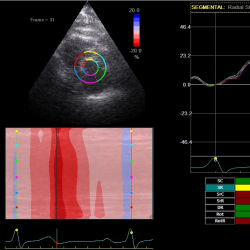

2D-echocardiography measurement was performed at rest in the left lateral decubitus position, using the Vivid 7 device (General Electrical-Vingmed Ultrasound AS, Horten, Norway) with 3.5 MHz transducers. Strain analysis was done by one investigator who was blinded to the results of the CAA examinations by using automated software Echo-PAC (GE Healthcare). The examination included standard measurements: left ventricular posterior wall (LVPW), left ventricular interventricular wall (LVIW), left ventricular end-diastolic diameter (LVEDD), left ventricular end-systolic diameter (LVESD), left ventricular end-diastolic volume (LVEDV), left ventricular end-systolic volume (LVESV), left ventricular ejection fraction (LVEF), early diastolic trans-mitral flow velocity (E), atrial systolic velocity (A), early diastolic mitral annular velocity (e′). 3 consecutive beats from standard positions (short axis, long axis, 4-chambers, 3-chambers, and 2-chambers views) were used for evaluation. Two-dimensional grayscale images were obtained at a frame rate of 60–80 Hz. According to the latest guidelines, we also measured strain and strain rate (SR) (Danaei et al., 2013). The investigator traced the LV endocardium manually, therewith it was tracked by the standard software automatically. Peak radial and circumferential strain and SR (systolic, early and late diastolic) were measured based on the short-axis view (Fig. 1) peak longitudinal strain and SR were measured based on apical four- (Fig. 2), two- and three-chamber views. Radial, longitudinal (GLS), circumferential global and regional strains were calculated as an average of measurements.

Fig. 1

Two-dimensional strain echocardiography, short-axis view.